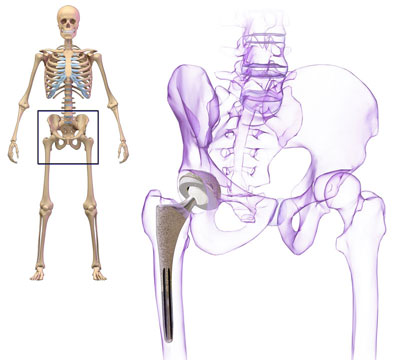

Charnley designed the first hip joint and in 1962 performed the first successful hip-replacement operation. His design used a femoral stem and ball made of steel and a hip socket made of Teflon, glued together using acrylic bone cement. Many improvements have been made since but Charnley set the standard and today 80,000 hip replacements are performed in Britain each year.

Hip replacement is a surgical procedure in which the hip joint is replaced by a prosthetic implant. Hip replacement surgery can be performed as a total replacement or a half replacement. Joint replacement orthopaedic surgery is generally conducted to relieve arthritis pain or in some hip fractures. A total hip replacement consists of replacing both the concave surface of the pelvis and the femoral head while half replacement generally only replaces the femoral head. Hip replacement is currently the most common orthopaedic operation.

Total Hip Replacement